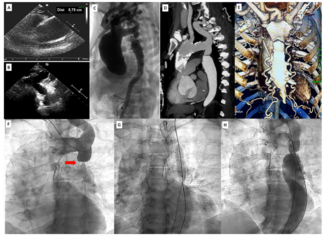

A 69-year-old man underwent coronary intervention for stenosis in the left main (LM) quadrifurcation lesion with SYNTAX score 23 (SYNTAX II score: coronary intervention 27.5, bypass surgery 33.5) 1 week after primary stenting in the right...